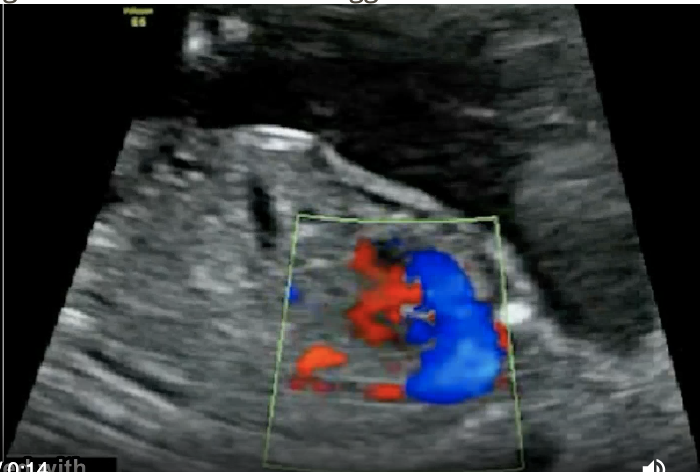

which intracranial anomalies is most commonly assoc w/fetal hydrops, ascites, and congestive heart failure

a) schizencephaly

b) holoprosencephaly

c) intracranial bleed

d) vein of galen aneurysm